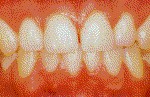

Salud.- Color rosa coral, la encía rodea firmemente al diente, no sangran.

Higiene bucodental

Una adecuada higiene bucodental desde la infancia deviene fundamental para conservar la dentadura, encías y boca en buenas condiciones. El abecé de los cuidados de la boca debe incluir el cepillado diario, el uso de hilo dental, una revisión periódica por parte del dentista y el control de la dieta (limitando el consumo de dulces). La labor de los progenitores es primordial para trasmitir unos correctos hábitos de higiene bucodental a los niños: hay que enseñarles cómo hacerlo y ser constantes en el empeño. Atrás quedó la política sanitaria basada en la extracción y la mutilación; hoy se apuesta por la prevención, aunque queda mucho por hacer: algo más de la mitad de los escolares de 14 años y más del 90% de los adultos tienen caries.